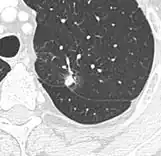

-

Part solid nodule.[9] -

Ground glass opacity nodule.[9]